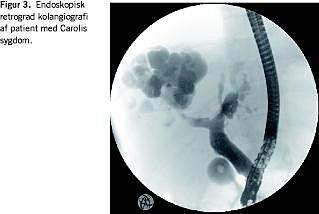

Parasitære cyster

Behandlingen af hydatidcyster varierer med deres Ghambi-klassifikation. Omdrejningspunktet er peroral behandling med albendazol. Behandlingen indledes en uge før intervention og fortsættes 1-6 måneder efter. Type I-II behandles med den såkaldte puncture aspiration injection reaspiration (PAIR)-teknik, som ved større cyster (> 6 cm), hvor risikoen for kommunikation med galdevejene er større, kan modificeres med anlæggelse af et grisehalekateter [10]. Cystevæske udtømmes ultralydvejledt, hvorefter der injiceres hypertont saltvand, som udtømmes efter 20 minutter. Ved større cyster efterlades grisehalekateteret som passiv drænage i et døgn, og hvis der ikke er tegn i drænvæsken til kommunikation med galdevejene, injiceres 96% ætanol. Kirurgisk behandling er sjælden, men kan overvejes ved cyster, som er svært tilgængelige for punktur eller de multilobulerede type III-cyster. Ved operativ behandling afskærmes peritoneum med servietter for at undgå spild af cystemateriale, hvilket er kritisk ved alle teknikker. Risikoen for kolangitis ved injektion i en biliær fistel er formentlig negligeabel. Tidligere tiders risiko skyldtes de initiale behandlingsmetoder med formaldehyd [6]. Andre cysteformer behandles med perkutan drænage og antiamøbemidler.